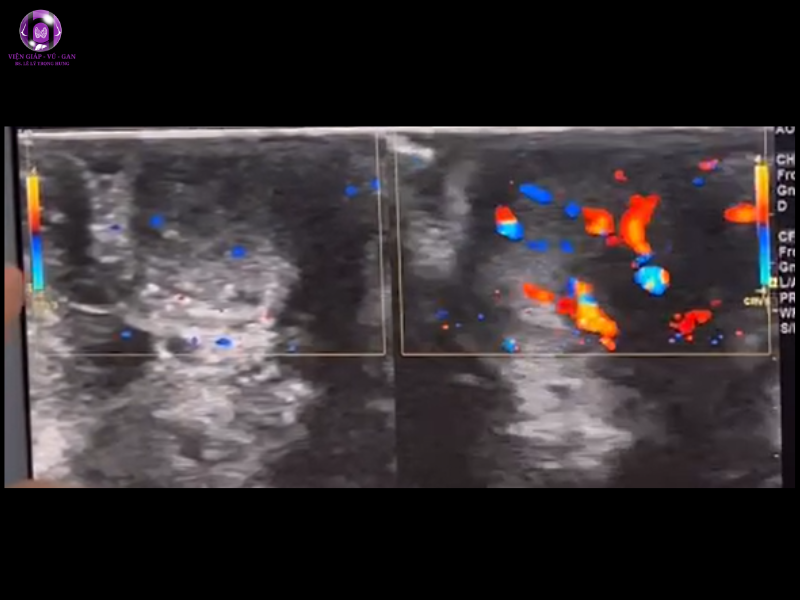

- Kết quả siêu âm:

- Núm vú trái to hơn phải, mất cấu trúc lớp và có hình ảnh tăng sinh mạch máu so với núm vú phải

- Ngay sau núm vú trái có cấu trúc echo kém, giới hạn không rõ, bờ gai, không vôi hoá, phân bố mạch máu ngoại vi, kt# 11x9mm ( BIRADS 4B)